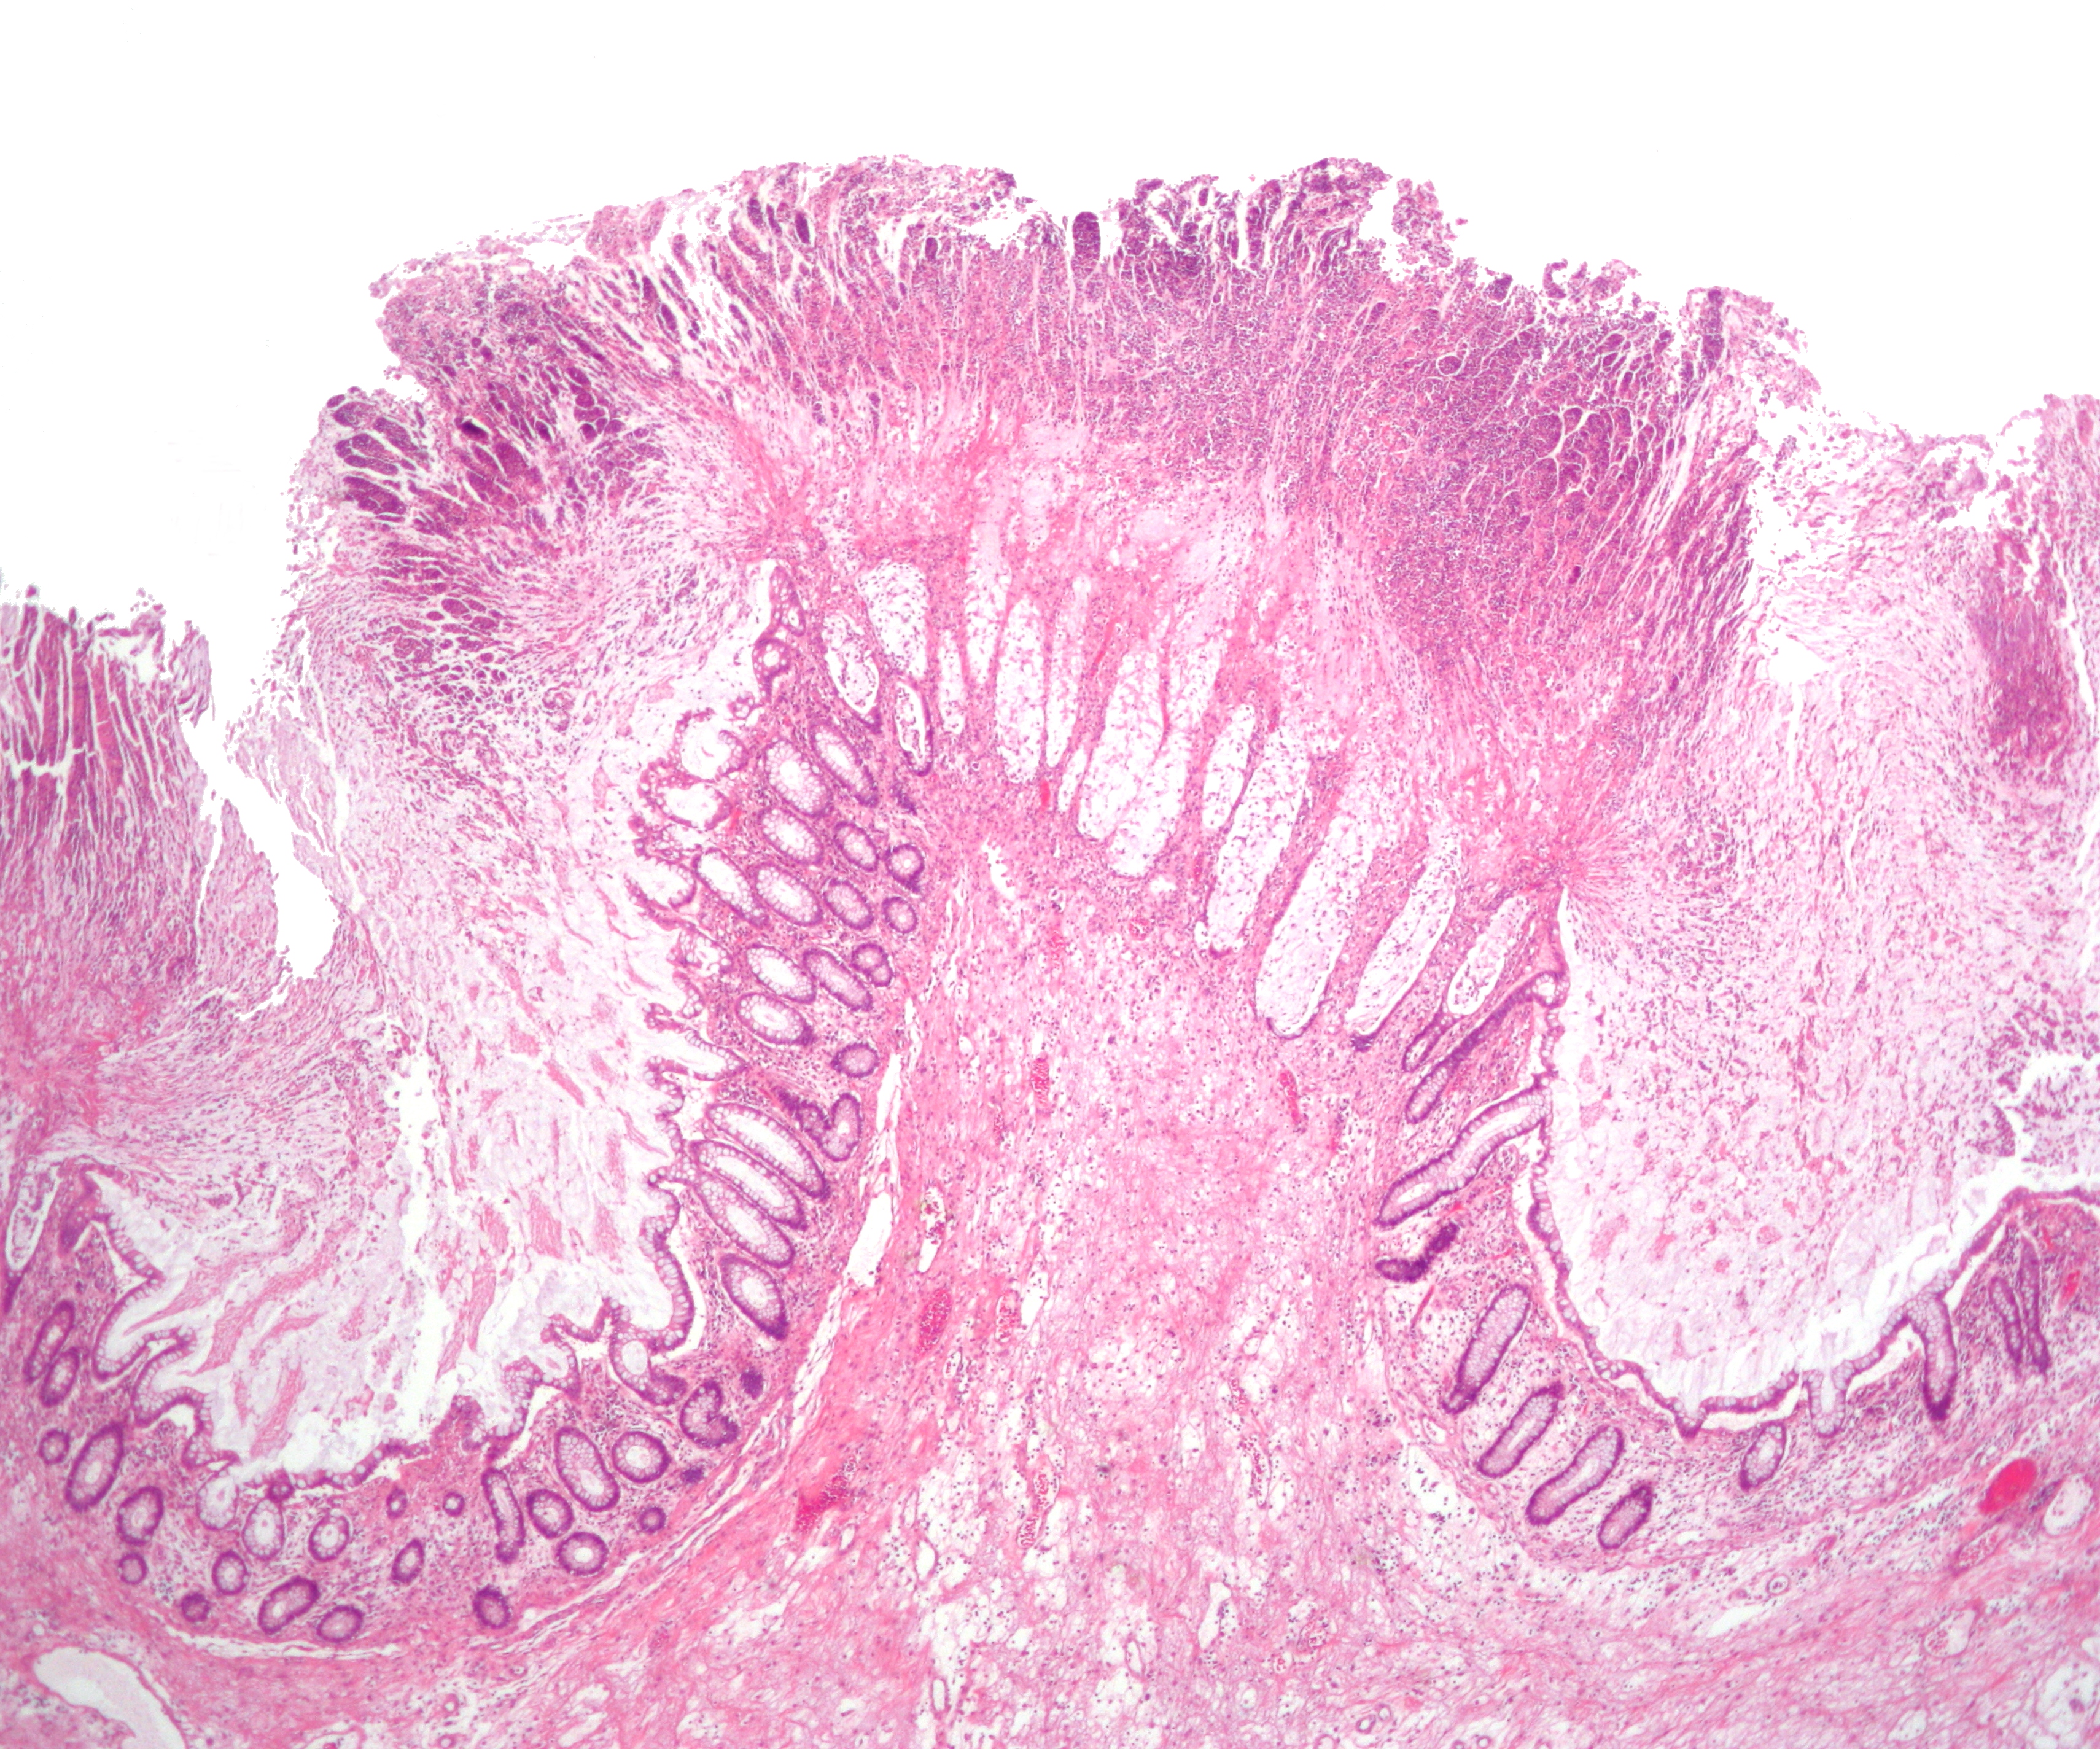

''C. difficile'' 대장염의 가성 막의 현미경 사진, 가성 막 대장염의 한 종류, H&E 염색

''C. difficile'' 독소를 검출하는 검사가 나오기 전에는, 결장경 검사나 S상 결장경 검사를 통해 진단하는 경우가 많았다. 결장 또는 직장 점막에서 "가성 막"의 출현은 이 질환을 시사하지만, 진단적인 것은 아니다.[46] 가성 막은 염증성 잔해물과 백혈구로 구성된 삼출물로 이루어져 있다. 현재도 결장경 검사 및 S상 결장경 검사가 사용되기는 하지만, 현재는 ''C. difficile'' 독소 존재 여부를 검사하는 대변 검사가 진단의 첫 번째 단계로 자주 사용된다. 일반적으로 독소 A와 독소 B 두 가지만 검사하지만, 이 균은 다른 독소도 여러 개 생성한다. 이 검사는 100% 정확하지 않으며, 반복 검사에도 위음성률이 상당하다.[47]